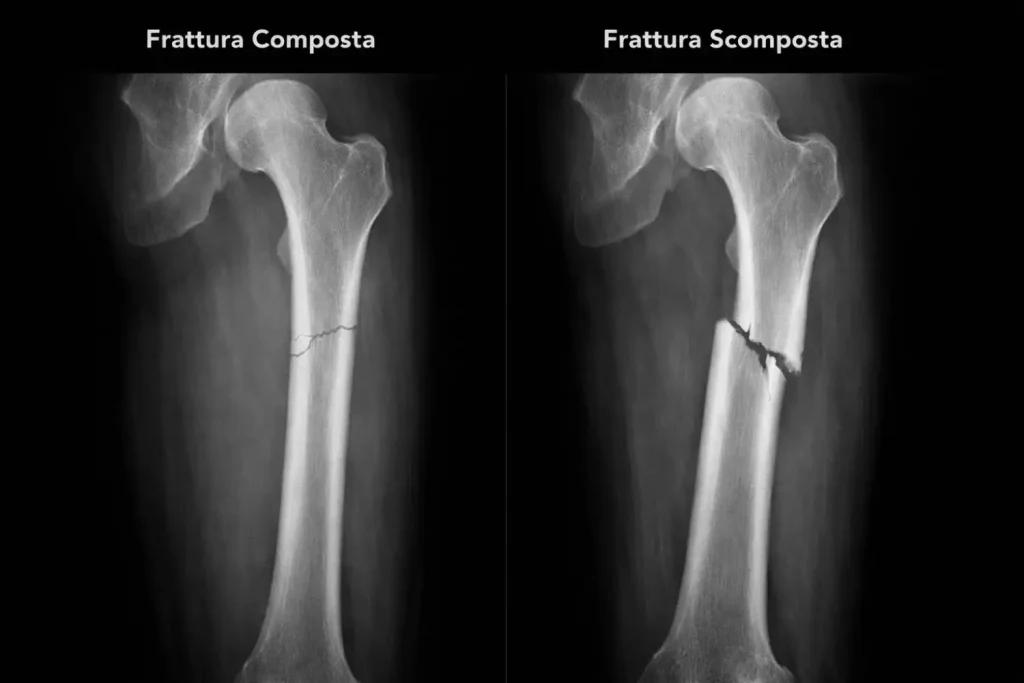

Una frattura composta è una rottura dell’osso in cui i frammenti ossei rimangono allineati nella loro posizione anatomica naturale. A differenza della frattura scomposta, l’osso non risulta deformato e non vi è dislocazione dei segmenti ossei.Questo non significa che la frattura sia “meno seria”, ma che il trattamento è generalmente più semplice e la guarigione più prevedibile.

La radiografia (RX) è l’esame di riferimento per diagnosticare una frattura composta.

Consente di visualizzare con precisione:

- La linea di frattura;

- l’allineamento dei frammenti ossei;

- l’assenza di scomposizione;